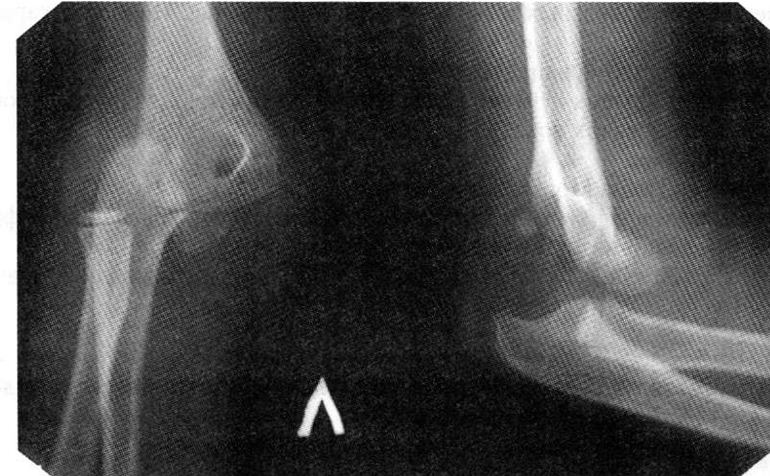

S53.0 Вывих головки лучевой кости

Вывих костей предплечья (рентгенограмма)